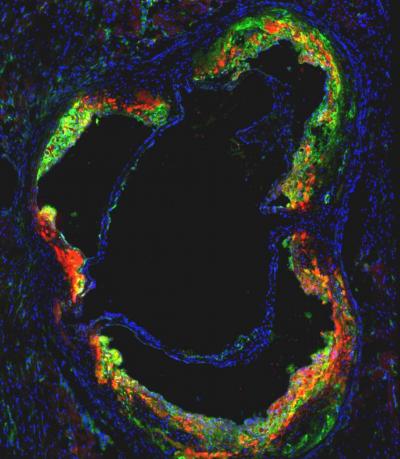

An international research team, led by Mount Sinai investigators, designed and tested a high-density lipoprotein (HDL) nanoparticle loaded with a statin drug. In mouse studies, they show this HDL nanotherapy is capable of directly targeting and lowering dangerous inflammation in blood vessels.

Oral statin medications used by millions of people today work primarily in the liver to reduce levels of unhealthy lipids, such as low density lipoproteins (LDL), that circulate in the blood. Statins also exert a very weak dampening effect on some inflammatory cells, foremost those called macrophages that hide within plaque in the arterial walls. It is this anti-inflammatory function that the researchers sought to bolster by designing their HDL nanotherapy.

Inflammation is the main driver of plaque buildup in arteries. Without inflammation, as well as lipid deposition in blood vessels, clots would not form. As inflammation progresses, macrophages secrete enzymes that degrade the walls of blood vessels, leading to a break in the vessel and the formation of clots. These clots can then clog arteries, leading to a heart attack or stroke.

According to Mount Sinai researchers, the best way to use their HDL nanotherapy is by injection after the clot that produces a heart attack or stroke has been treated. The HDL nanoparticle would deliver the statin directly to macrophages that are driving the inflammatory response. "This could potentially and very rapidly stabilize a dangerous situation," Dr. Mulder says. "In addition, after discharge, patients would continue to use their oral statins to control LDL in their blood."

"Our study also confirms that the HDL nanoparticle is not seen as a foreign invader by the body's immune system and that it has an inherent and natural affinity to target plaque macrophages," says Jun Tang. "Our experiments demonstrated a very rapid reduction in inflammation in mice with advanced plaque buildup."